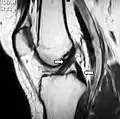

Posterior cruciate ligament

The posterior cruciate ligament (PCL) is a ligament in each knee of humans and various other animals. It works as a counterpart to the anterior cruciate ligament (ACL). It connects the posterior intercondylar area of the tibia to the medial condyle of the femur. This configuration allows the PCL to resist forces pushing the tibia posteriorly relative to the femur.